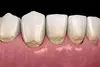

Elle se caractérise par une cavité située dans la partie cervicale de la dent, c’est-à-dire au niveau de la jonction entre la couronne et la racine. Cette lésion est brillante, dure au sondage et peut prendre une légère coloration brune.